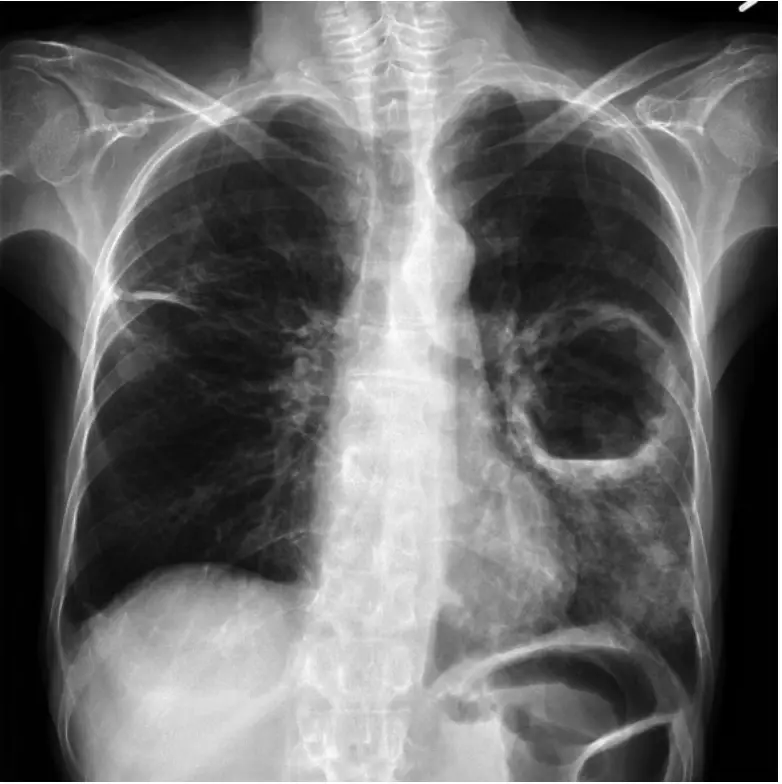

王先生 72歲,有糖尿病,此次因咳嗽、咳痰、發燒、呼吸急促,住院時胸部 X 光如圖所示,其最可能之臨床診斷為何?

胸部 X 光「空洞併液平面」(air-fluid level) 的判讀與肺部化膿性感染之鑑別診斷。

空洞病灶內若出現明顯液平面,表示病灶內同時存在氣體與液體。位在肺實質者稱 lung abscess;位在胸膜腔者屬 empyema。影像「空腔壁厚、周圍為肺實質浸潤」最典型的就是肺膿瘍。

C. 肺膿瘍 (正確)

- 定義:肺實質遭細菌(多為厭氧菌、Klebsiella 於糖尿病者)破壞形成含膿腔。

- 影像:圓形或橢圓形厚壁空洞,內見水平液面,外周常併局部肺炎式浸潤。

- 臨床:高齡、糖尿病、吞嚥或意識障礙→易吸入,出現高燒、咳大量惡臭膿痰、呼吸急促,與題目完全符合。